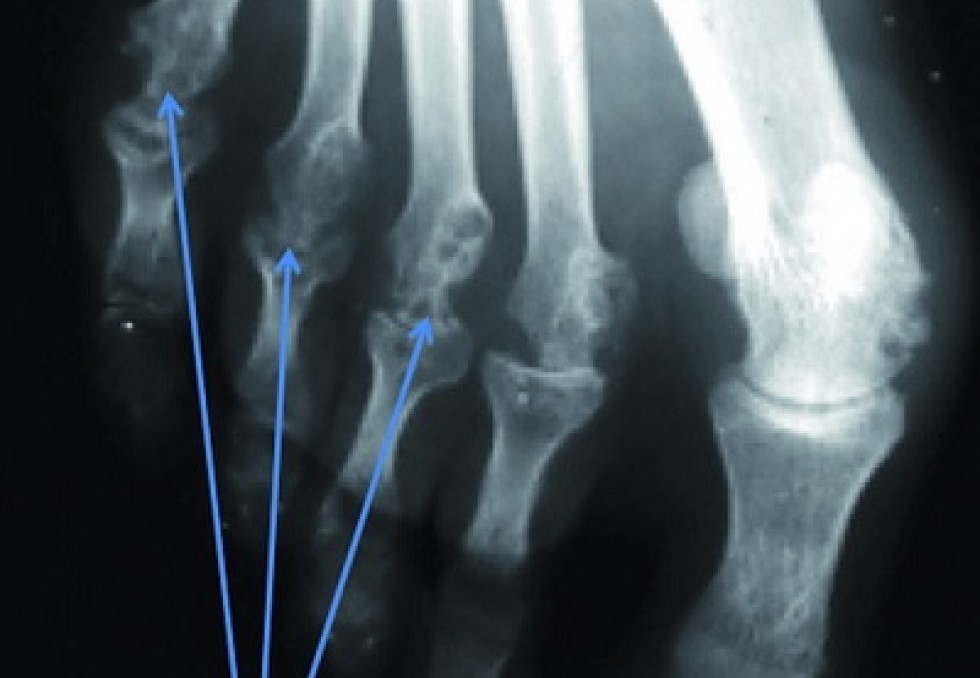

Le dernier né est Kevzara (sarilumab), le premier anticorps monoclonal anti-IL6R en administration sous-cutanée toutes les deux semaines. Sa première indication est la polyarthrite rhumatoïde (PR) active, modérée à sévère, seul ou en association au méthotrexate (MTX) en cas de réponse insuffisante ou d’intolérance au MTX. Pour annoncer ce lancement, Sanofi Genzyme, désormais unité opérationnelle mondiale de Sanofi pour les maladies rares, la SEP, l’immunologie et l’oncologie, avait convié Gérard Thibaud, Président de l’Association nationale de défense contre l’arthrite rhumatoïde (Andar). Entendre la voix du patient dans une telle pathologie est essentiel afin de comprendre l’importance de l’innovation thérapeutique. Victime de cette maladie depuis plus de 40 ans, ce patient a bénéficié en 2010 de sa première biothérapie : "un véritable miracle", dit-il, après tant d’années marquées par les déformations articulaires que ni la chirurgie palliative ni le MTX ou les corticoïdes n’avaient pu éviter. Pour la première fois depuis des décennies, grâce à un premier antiTNF-alpha, Gérard Thibaud pouvait enfin faire de longues marches, porter ses petits-enfants, lui qui n’avait jamais pu porter son enfant. Jusqu’à la première rechute par un phénomène d’échappement thérapeutique, un événement encore plus difficile à vivre, selon lui, que l’annonce de la maladie. C’est à ce moment-là qu’on comprend toute l’importance d’un traitement biologique supplémentaire qui permettra de sortir de l’impasse thérapeutique. Aujourd’hui, Gérard Thibaud en est à sa 3e biothérapie avec une qualité de vie satisfaisante.   Bloquer la capacité destructrice de l’interleukine 6 Les Prs Alain Cantagrel (CHU de Toulouse) et René-Marc Flipo (CHU de Lille), respectivement président et secrétaire général de la Société française de rhumatologie, se sont relayés pour présenter ce nouveau biomédicament qui doit permettre d’atteindre l’objectif thérapeutique de tout cas de PR : l’obtention et le maintien de la rémission marquée par l’absence de signes et de symptômes d’activité inflammatoire. Sept essais multicentriques, notamment l’étude Mobility, incluant un total de 2 887 patients, ont assuré le plan de développement de Kevzara dont bénéficient déjà plus de 5 000 patients dans 15 pays. Le sarilumab est un anticorps monoclonal humain qui se lie de manière spécifique aux récepteurs solubles et membranaires de l’interleukine 6 (IL-6), une cytokine retrouvée à un taux élevé dans les articulations des patients atteints de PR et jouant un rôle important dans la destruction articulaire. Kevzara s’administre en sous-cutané toutes les deux semaines. Le stylo prérempli peut être conservé à température ambiante durant 15 jours, donnant une autonomie d’un mois à un patient ayant retrouvé sa mobilité.